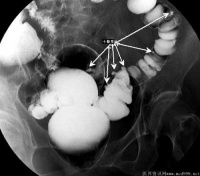

结肠憩室炎

结肠憩室是指肠粘膜经肠壁肌层缺损处向外形成囊状突出的病理结构。多个憩室的存在则称之为结肠憩室病。

憩室绝大多数为后天形成的,多位于乙状结肠,盲肠、升结肠也不少见。